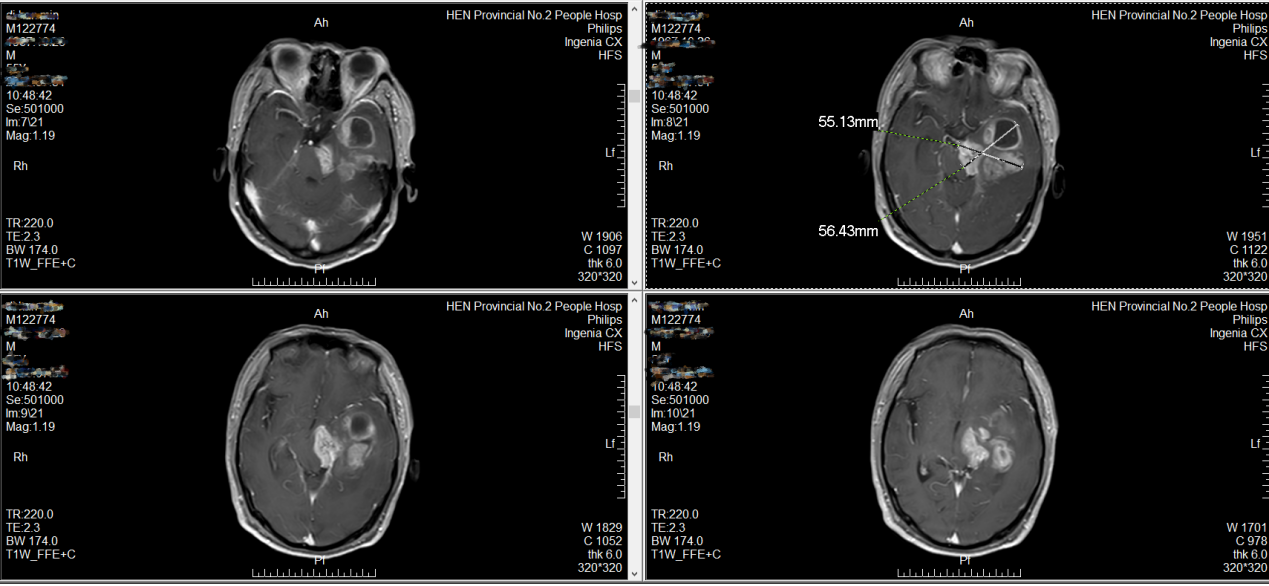

该院神经外科主任、主任医师周玉璞结合检查结果发现,患者不完全失语,右侧面瘫,右侧肢体轻偏瘫;核磁共振检查显示:左侧颞叶及左侧丘脑、左侧基底节区多发占位,肿瘤侵犯脑干,脑干及小脑幕切迹区受压明显,肿瘤大小约为55mm×56mm×56mm。周玉璞当即诊断患者罹患胶质瘤可能性大。